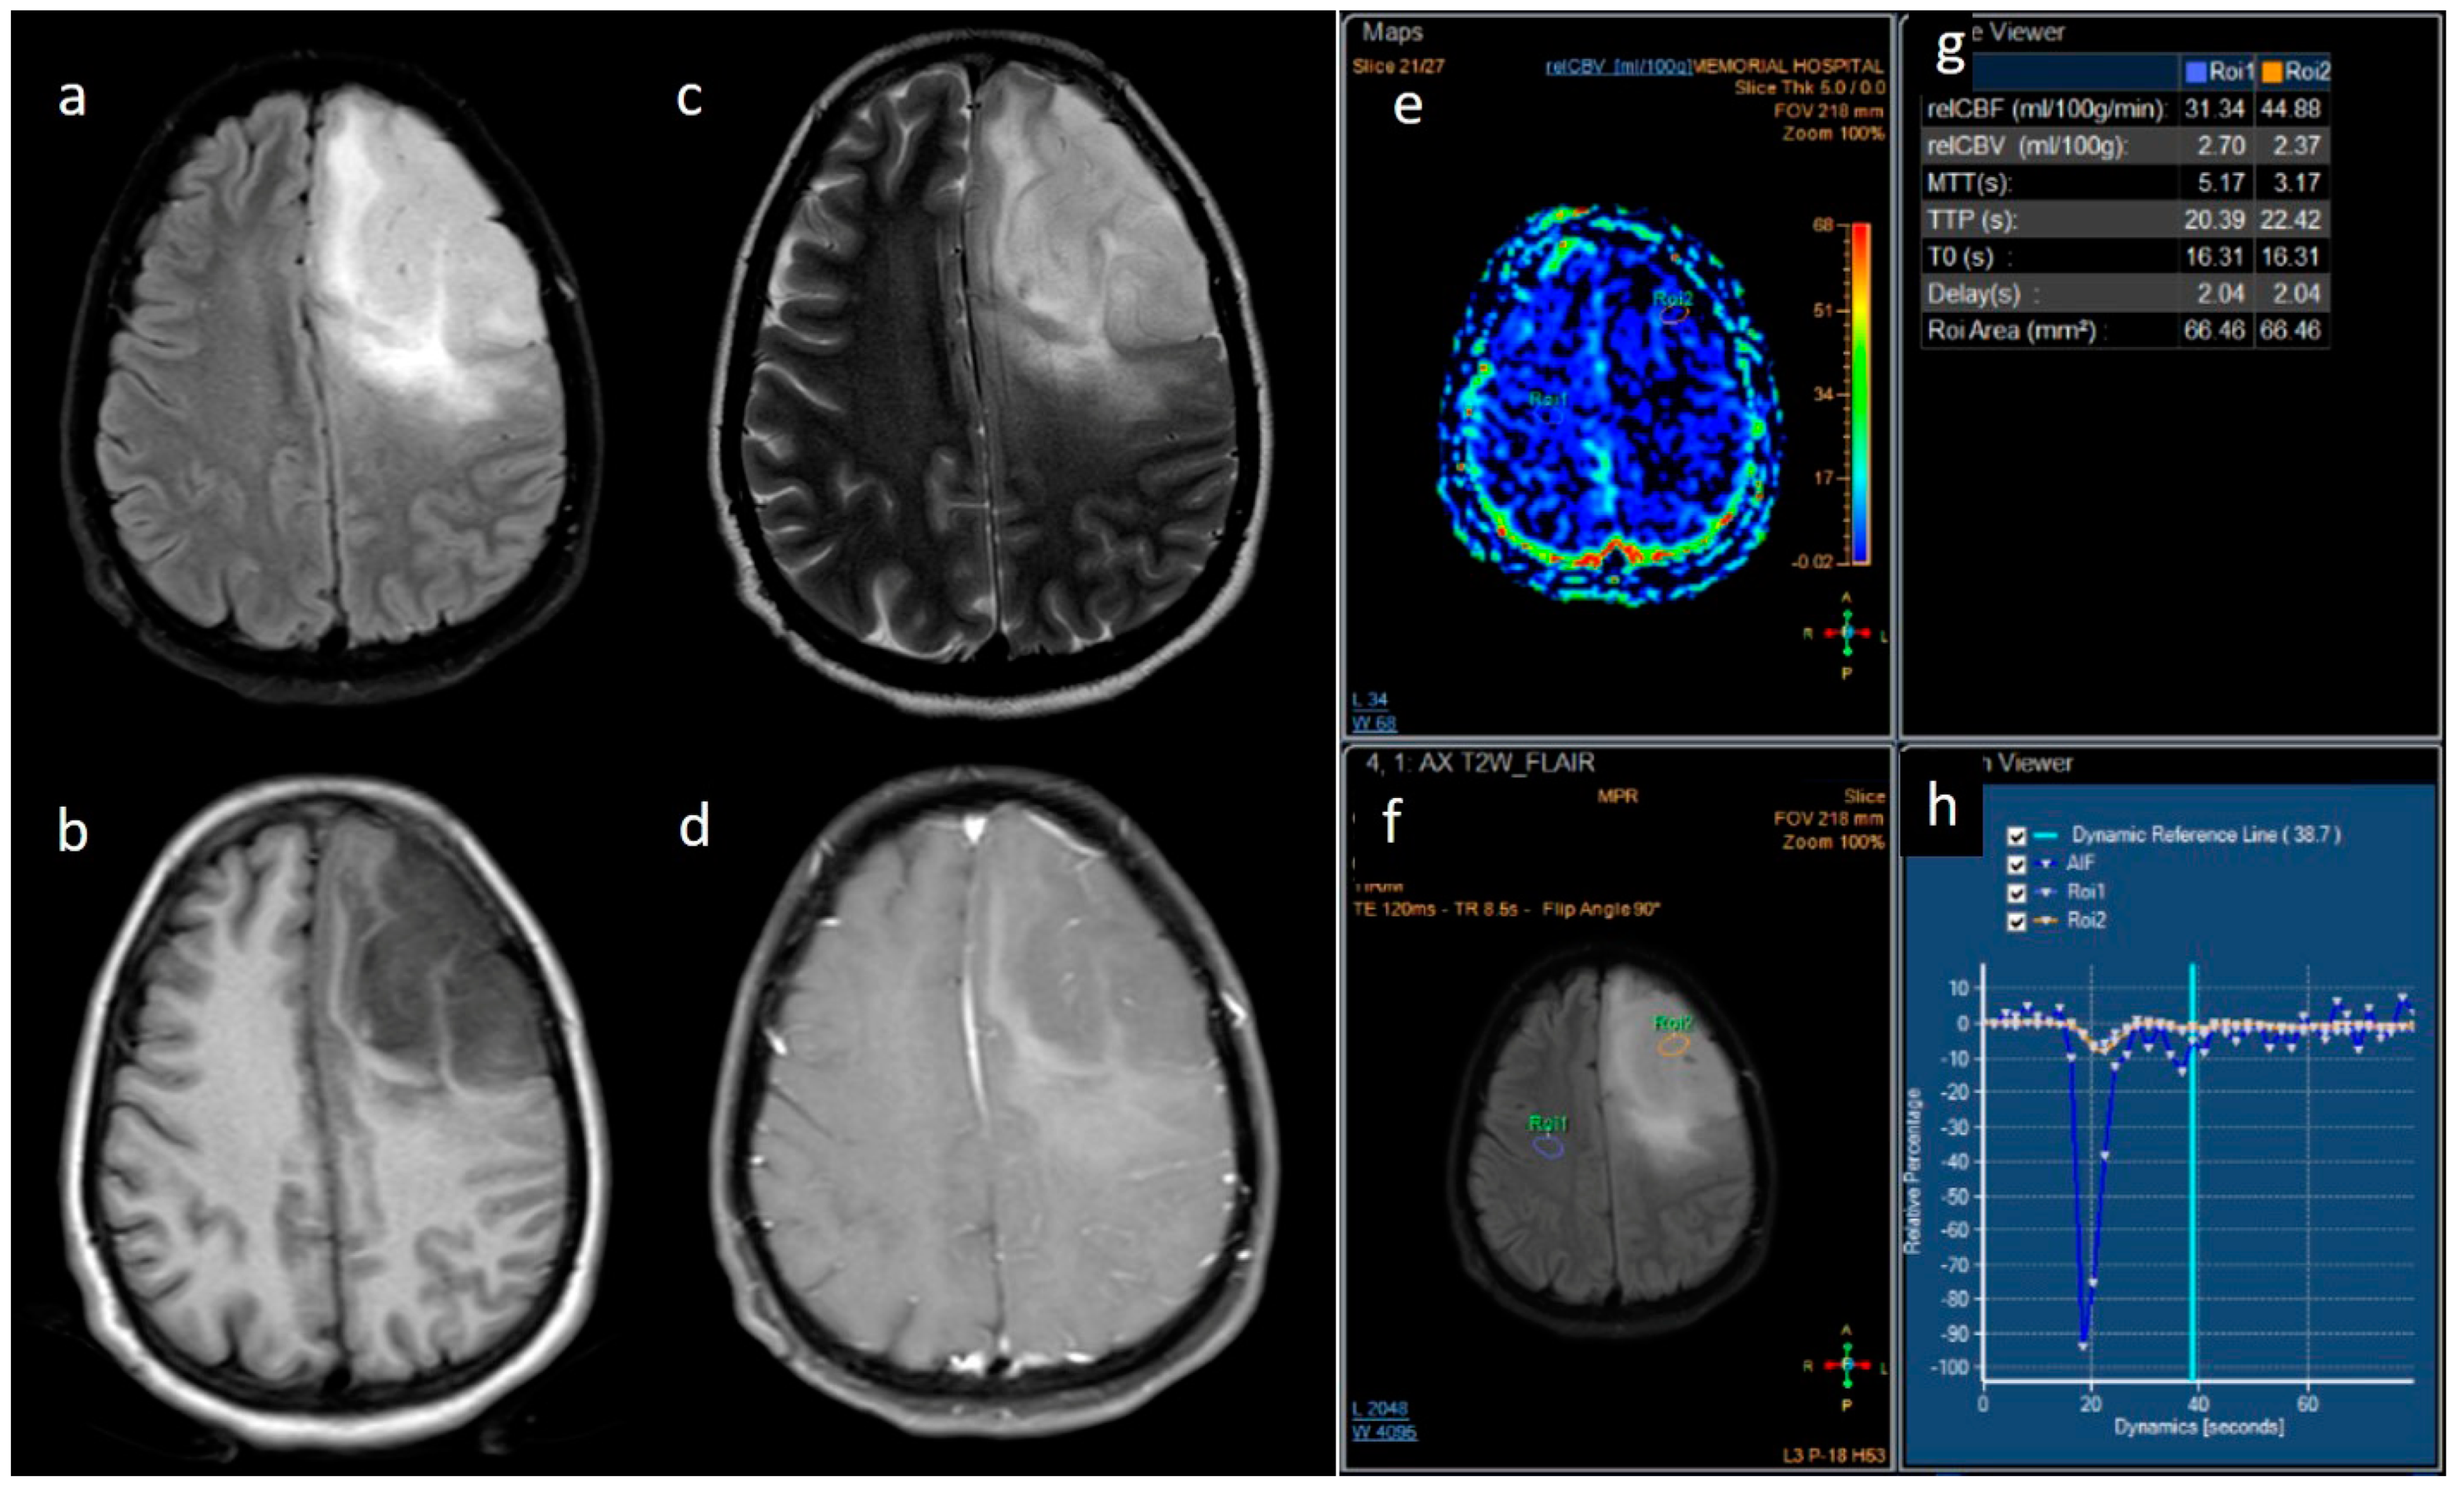

| rCBV | Median (IQR) | 1.8 [1.4–2.0] | 2.6 [1.9–3.5] | 0.001 |

| rCBV | <=2.0 | Reference | ||

| >2.0 | 0.12 | [0.03; 0.56] | 0.007 |